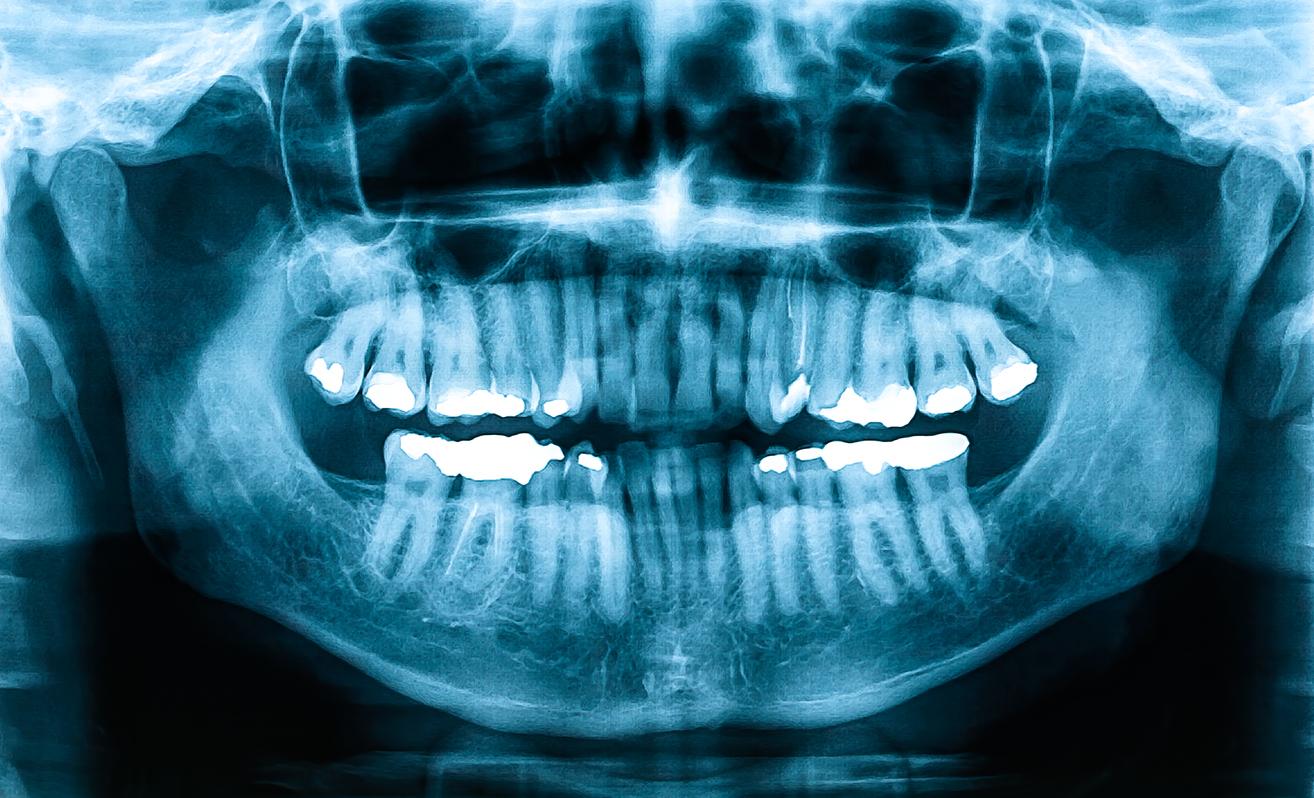

Pour parvenir à cette conclusion, les chercheurs ont utilisé la tomodensitométrie à faisceau conique (CBCT), un type de rayons X, pour mesurer la densité osseuse dans la tête et le cou de 38 participants adultes, dont la moitié souffrait d'apnée du sommeil. Les volontaires touchés par l'apnée du sommeil avaient une densité minérale osseuse significativement plus faible que les participants sans condition.

"Si un patient a reçu un diagnostic d'apnée du sommeil, cela peut influencer la planification et la gestion du traitement. L'imagerie CBCT est devenue une partie intégrante de la pratique orthodontique quotidienne et pourrait être utilisée comme outil de dépistage de la faible densité minérale osseuse", a-t-elle ajouté. Selon la chercheuse, "les orthodontistes pourraient alors informer leurs patients de leur propension à une faible densité minérale osseuse et les encourager à consulter davantage leur médecin." Cependant, de futures recherches avec des échantillons plus importants sont encore nécessaires pour confirmer ces résultats.